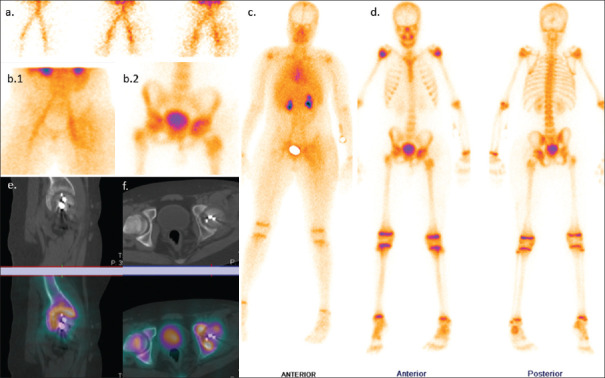

Uomo di 35 anni con lombalgia in peggioramento da 6 mesi e recente insorgenza di dolore alla spalla sinistra, associati a inappetenza e malessere. È stata eseguita una scintigrafia ossea trifasica con 99mTc-MDP.

La fase di flusso ha mostrato un’ipervascolarizzazione a livello delle vertebre L3-L4 (a). Le immagini statiche di blood-pool (b. 1) e tardive (b. 2) della regione lombare hanno evidenziato un aumentato accumulo ematico e una captazione tardiva del tracciante nella medesima regione a livello L3-L4. L’immagine whole-body di blood-pool (c) e le immagini tardive (d) acquisite dopo 3 ore hanno mostrato un’aumentata captazione a livello delle vertebre L3-L4, dell’articolazione sterno-claveare sinistra e del manubrio dello sterno. Le immagini SPECT-TC della vertebra L4 (e) hanno rivelato una lesione distruttiva con interessamento dei tessuti molli pre- e paravertebrali; reperti simili di distruzione e raccolta fluida sono stati notati nell’articolazione sterno-claveare sinistra (f). Nella lesione vertebrale si osserva un sequestro a bottone (freccia nera). La RM eseguita 2 giorni dopo ha confermato una spondilodiscite.